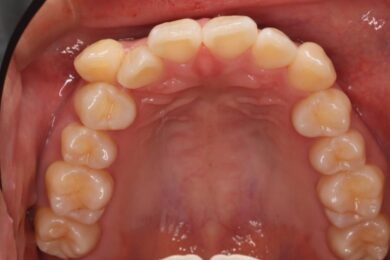

八重歯・叢生 マウスピース矯正(インビザライン)26歳女性 非抜歯

「前歯のガタガタ(叢生)と八重歯を治したい」を主訴に来院された患者様です。上下の歯にIPRを加え、歯列弓の拡大を行い、非抜歯で前歯のガタガタを整えました。顎間ゴムを用い、咬み合わせも改善されています。アライナーの装着時間が長く、チューイをしっかり使用していただけたため、非常に短時間で仕上がりました。

• 治療後